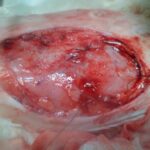

Infeksion i rende i mitres (piometer)

Qenushja ne foto erdhi ne klinike pasi ishte sorollatur ne nje spital veterinar per ti bere shume analiza (natyrisht kundrejt pagesave) ne nje kohe qe ato ishin te pa nevojshme sepse pamja ishte e qarte dhe duhej nderhyrje kirurgjikale urgjente e cila u krye ne kliniken tone. Rezultati duket nga fotot , qenushja shpetoi dhe tashme gezon shendet te plote.